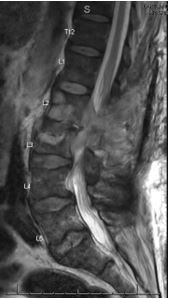

Case Presentation: A 69-year-old male with a significant past medical history of rheumatoid arthritis on methotrexate presented with acute-on-chronic lumbar pain. Initial imaging revealed an L3 compression fracture, with findings suggestive of discitis or osteomyelitis at L2-L3. MRI confirmed discitis/osteomyelitis, along with an epidural abscess and bilateral psoas abscesses. Further imaging also revealed cavitary pulmonary lesions. The patient tested positive for PPD during routine screening for initiation of infliximab therapy (Remicade). Subsequent diagnostic studies, including QuantiFERON-TB Gold and blood cultures, were unremarkable. Empiric antibiotic therapy with ceftriaxone and vancomycin was initiated, later replaced by daptomycin due to clinical suspicion of bacterial osteomyelitis. A comprehensive workup, including CT imaging and bronchoscopy with bronchoalveolar lavage (BAL), was pursued. Cultures ultimately identified MAC from both the lumbar abscess and BAL samples. Antibiotic therapy was adjusted to a regimen of clarithromycin, ethambutol, rifabutin, and amikacin. Despite surgical drainage and ongoing antimicrobial therapy, the patient’s treatment course is projected to extend over 12 to 18 months, with close monitoring for clinical and radiologic response.